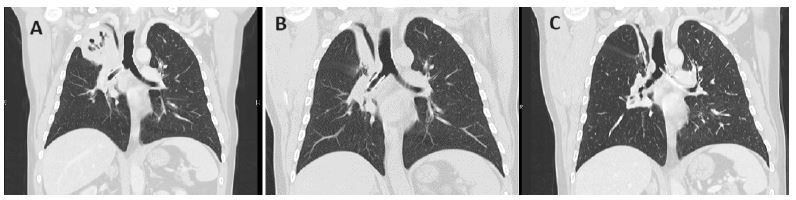

A rigid bronchoscopy was then performed and a silicone stent was placed at the level of the right main bronchus and intermediate bronchus (Figure 1A). The patient started chemotherapy, with the intention to go on to concomitant chemo-radiotherapy, but at the end of the second cycle there was no reduction in lung mass or adenopathy and the disease was considered not eligible for concomitant radiotherapy due to cardiac proximity and patient started pembrolizumab.

The patient had a great clinical and imaging improvement (with partial response) after 6 months of pembrolizumab (Figure 1B). A bronchoscopy was performed to review the need of maintaining endobronchial stent, but as it was still fixed, not displaced and permeable, it was decided to not remove. Five months later, clinically, the patient had more cough, with no other symptoms. He performed the usual follow-up CT scan that continued to show a great oncology response (partial), but the right main bronchus stent was migrated to the left main bronchus (Figure 1C). The stent was then removed from the left main bronchus and patient maintained pembrolizumab.

Figure 1: Thoracic CT Scan showing a upper lobe mass causing total atelectasis of the right upper lobe and a silicone stent in the right main bronchus (A); partial response to pembrolizumab with a decrease in the size of the mass in the right upper lobe-stent is still in the right main bronchus (B); maintenance of the partial response to pembrolizumab, with an even more marked reduction in atelectasis in the right upper lobe, now with migration of the stent to the left main bronchus (C).